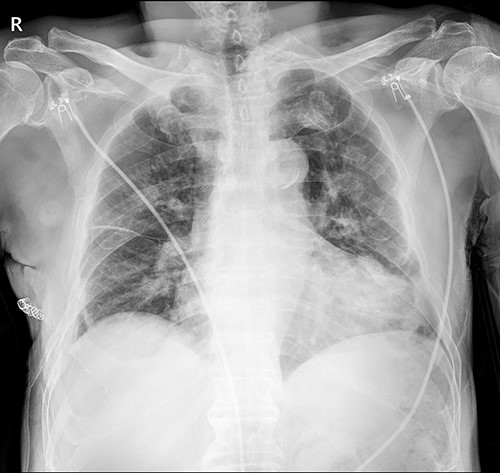

The patient underwent plate removal surgery on 24 February 2022. The operation was performed routinely. Under general anesthesia, a small incision was made on the previous operation scar. After sufficiently dissecting surrounding tissues and muscles, we skimmed implants off the rib cage. Then, a seven-French sizes (FR) drainage catheter was placed below the serratus anterior muscle (SAM) to manage potential minor complications. Because we usually do not invade the rib cage during plate removal operations, there was no need to be concerned about lung injury. The patient was discharged on hospital Day 2 with the submuscular drainage catheter removed (Fig. 2.).

Immediate postoperative chest X-ray after plates removal (24 February 2022).